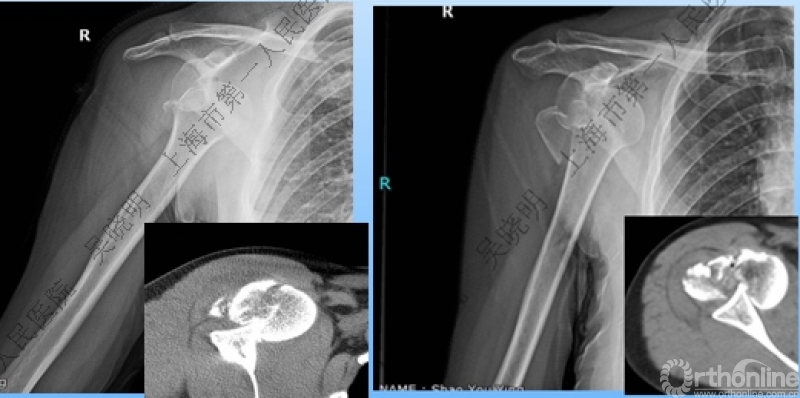

警惕孤立性向下移位的大结节骨折

外翻压缩型肱骨近端骨折

钢板固定

X线是孤立性向下移位的大结节,一定要小心,多伴有肱骨外科颈骨折

全麻下闭合复位,钢板固定